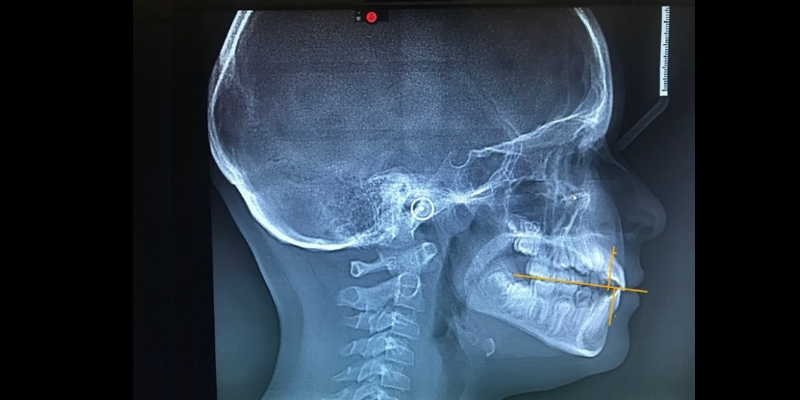

Anterior/Posterior Dimension

Cephalometric images can identify anterior/posterior deficiencies (Fig. 1). Witts Analysis indicates this child is maxillary deficient, stressing the importance of early orthodontic intervention. Failure to correct this now potentially creates a future where the soft palate may impinge upon the airway, resulting in a sleep disorder and other health-related sequelae. The same can be evident for a retrognathic mandible, potentially forcing the tongue back into the throat and pharyngeal region, impinging on the airway.

Both children and adults display deficiencies in the anterior/posterior dimension, a common finding in sleep-related disordered (SRD) patients due to improper growth of the maxilla and mandible.